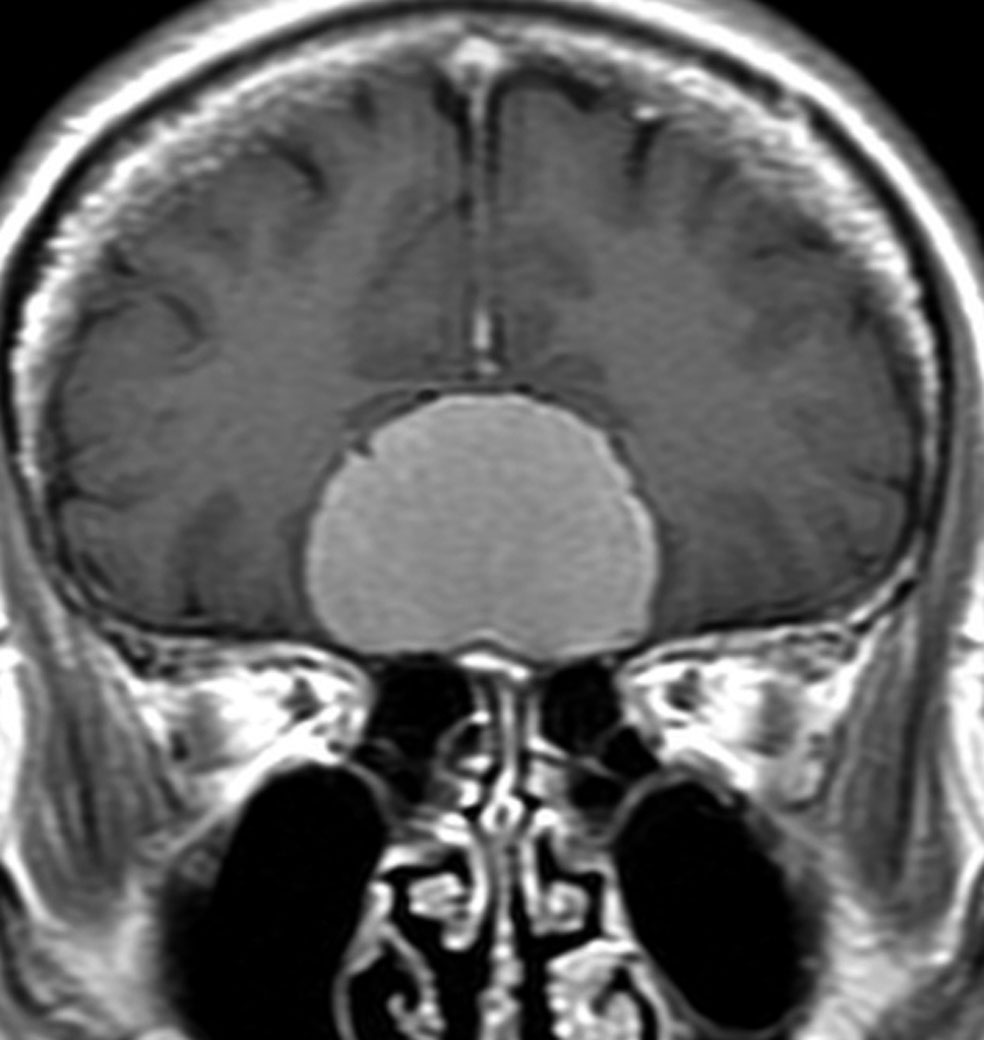

上矢状洞髄膜腫 superior sagittal sinus meningioma

上矢状洞を埋め尽くすように増大して,頭蓋骨浸潤が著しい髄膜腫ですが,ごく軽度の右足脱力以外に何の症状もありません。上矢状洞はゆっくり閉塞すれば,このような頭頂部から後頭部にわたる広範閉塞でも,静脈還流に障害がない場合が多いといえます。大脳の前半部の血流は前頭葉表面の皮質静脈から海綿静脈洞に側副路を形成しています。頭蓋内圧亢進所見もなく,これらはこの髄膜腫がゆっくり増大したということを示唆しています。

手術直後の画像です。全部いっぺんに摘出するのは無理なので,まず前から80%くらいの腫瘍を摘出しました。肥厚した骨はチタンプレートで置き換えてあります。後頭部の上矢状洞内と大脳鎌に少し残りましたが,この6ヶ月後に2回目の開頭術をして全摘出しました。結果的にこの例では,上矢状洞を冠状縫合のあたりから,静脈洞交会まで壁ごと全部摘出しましたが,脳浮腫も何も生じませんでした。腫瘍の両側にある皮質静脈 cortical veinsを損傷しないことが肝要です。

右の病理像は,頭蓋骨浸潤している部分 ですが,骨破壊は良性髄膜腫に特徴的な骨内浸潤像です。この骨浸潤像は悪性像とはいえません。MIB-1は高いところで8%、低いところで3%程度です。